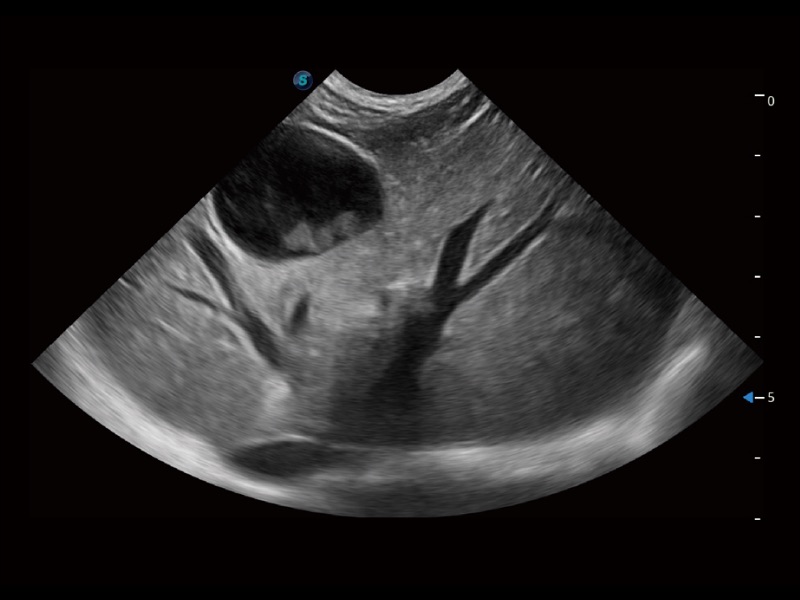

大型犬、马科、农场动物及大型异宠动物

通过创新的 Matrix E自适应滤波器和超长时间域算法,极大提升超低速微细血流的检出能力,同时更精准地滤除软组织和噪声信号,为兽用医生提供以往无法通过常规血流获得的疾病诊断信息。

ProPet 70专为动物医生设计,对不同的动物体型和生理结构作出了针对性的优化。通过动物影像专用软件,可满足个性化的应用需求,帮助动物医生获得更精确的诊断数据。

为精细结构及组织边缘提供高清晰度的图像和更大的成像视野。帮助减轻医生的用眼疲劳,快速精准获得测量的数据。